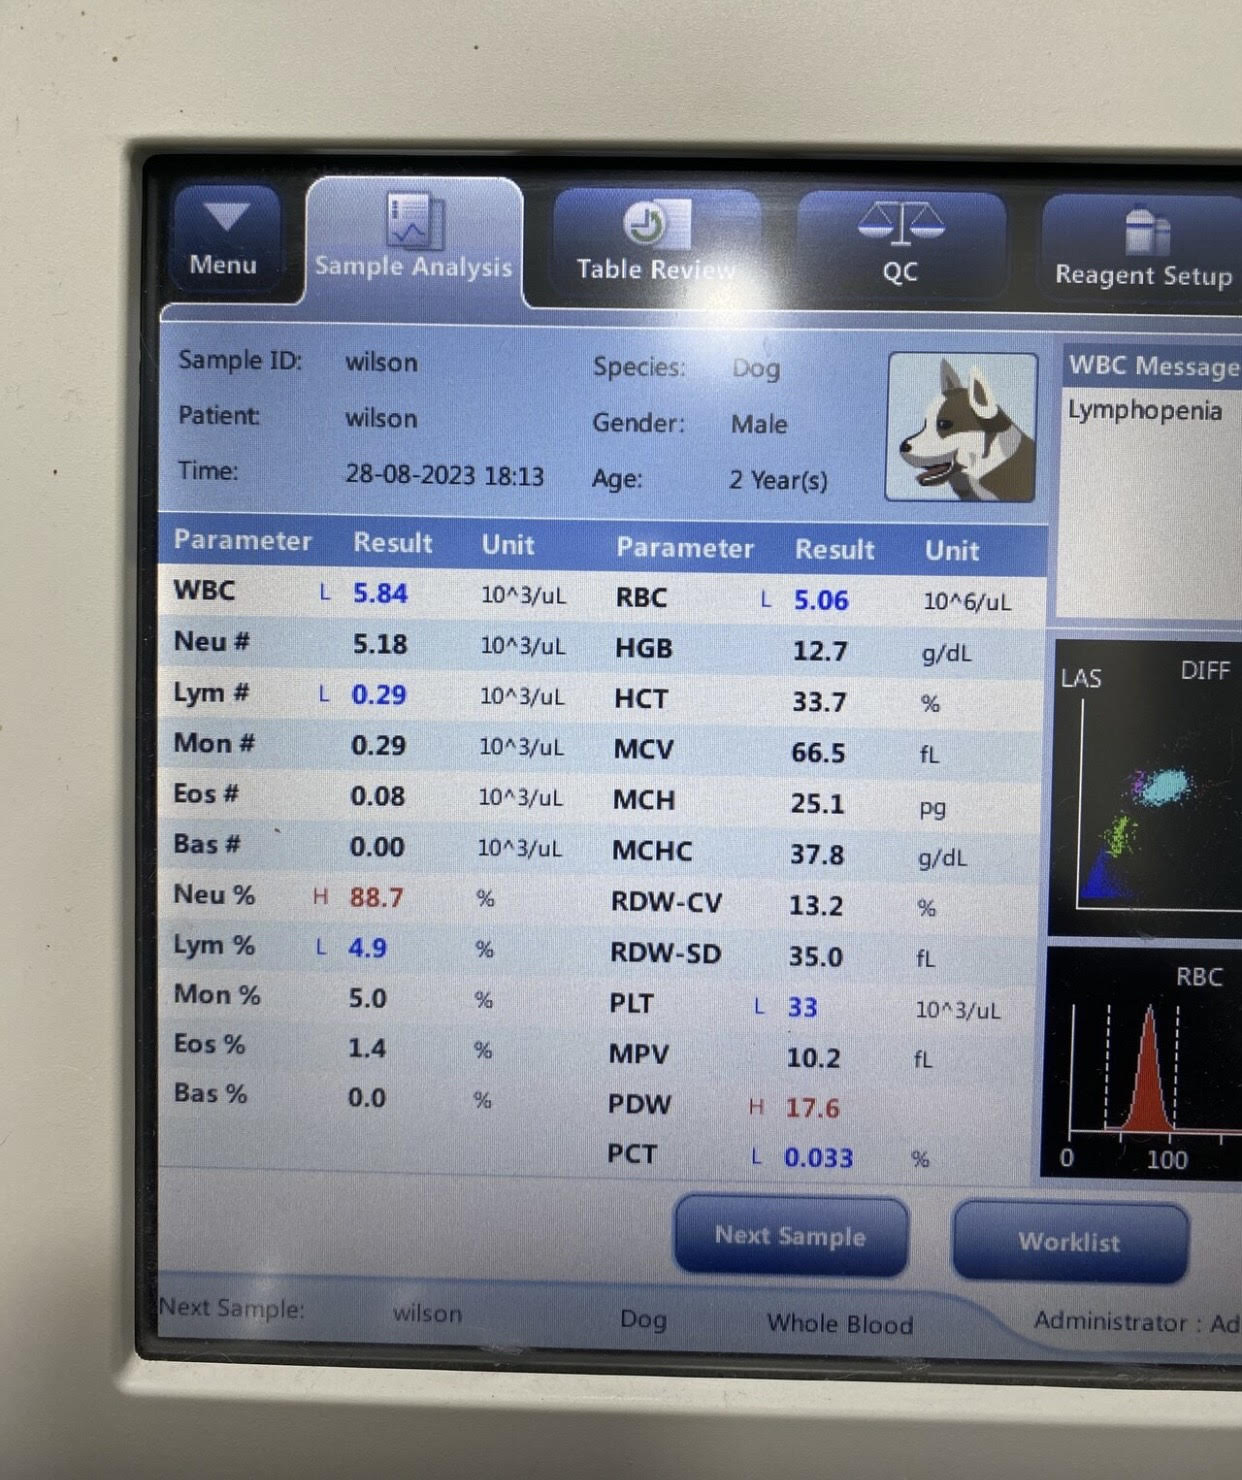

تشخیص آناپلاسموزیس در سگ ها :

تشخیص آناپلاسموزیس در سگ ها :

آناپلاسموز اغلب با آزمایش خون برای تشخیص آنتی بادی ها تشخیص داده می شود البته یک آزمایش آنتی بادی مثبت لزوماً نشان دهنده عفونت فعال نیست که نیاز به درمان دارد، بلکه میتونه نشان دهنده مواجهه قبلی سگ با کنه باشه که می تونه تا چندین ماه قابل تشخیص باقی بمونه